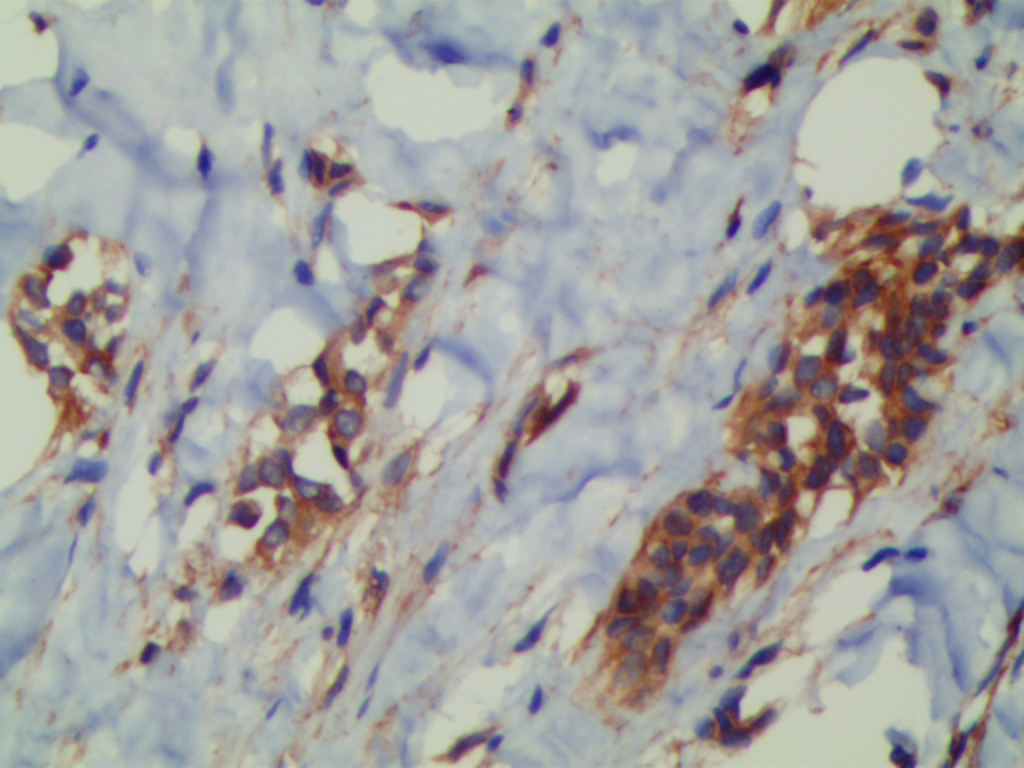

免疫组织化学染色:

E-cadherin:约 85%的 ILC 呈阴性,约 15%可见部分膜阳性或浆阳性。E-cadherin 阳可见更高概率的淋巴-血管浸润和混合性组织学模式。Catenins:E-cadherin 阴性 ILC 亦缺乏表达 α-、β-及 γ-catenins,P120 显示弥漫性胞浆表达;多数 E-cadherin 阳性 ILC 缺乏 1 种或更多 catenins 的膜表达,但可显示胞浆表达,多数显示 P120 胞浆表达。 约 90%以上的 1 级及 2 级 ILC 及 80%的 3 级 ILC 呈 ER 阳性,若 ILC 呈 ER 阴性,可能是假阴性或其他诊断(如:转移性黑色素瘤或淋巴瘤)。 HER2:过表达极其罕见(少于 1%的病例),3 级 ILC 除外。约 25-50%的 3 级 ILC 可呈阳性。部分病例可见边缘增强,不应被过度理解,FISH 可有助于证实是否有 HER2 扩增。 GCDFP-15:常阳性,尤其伴多形性、大汗腺或印戒细胞形态的 ILC。